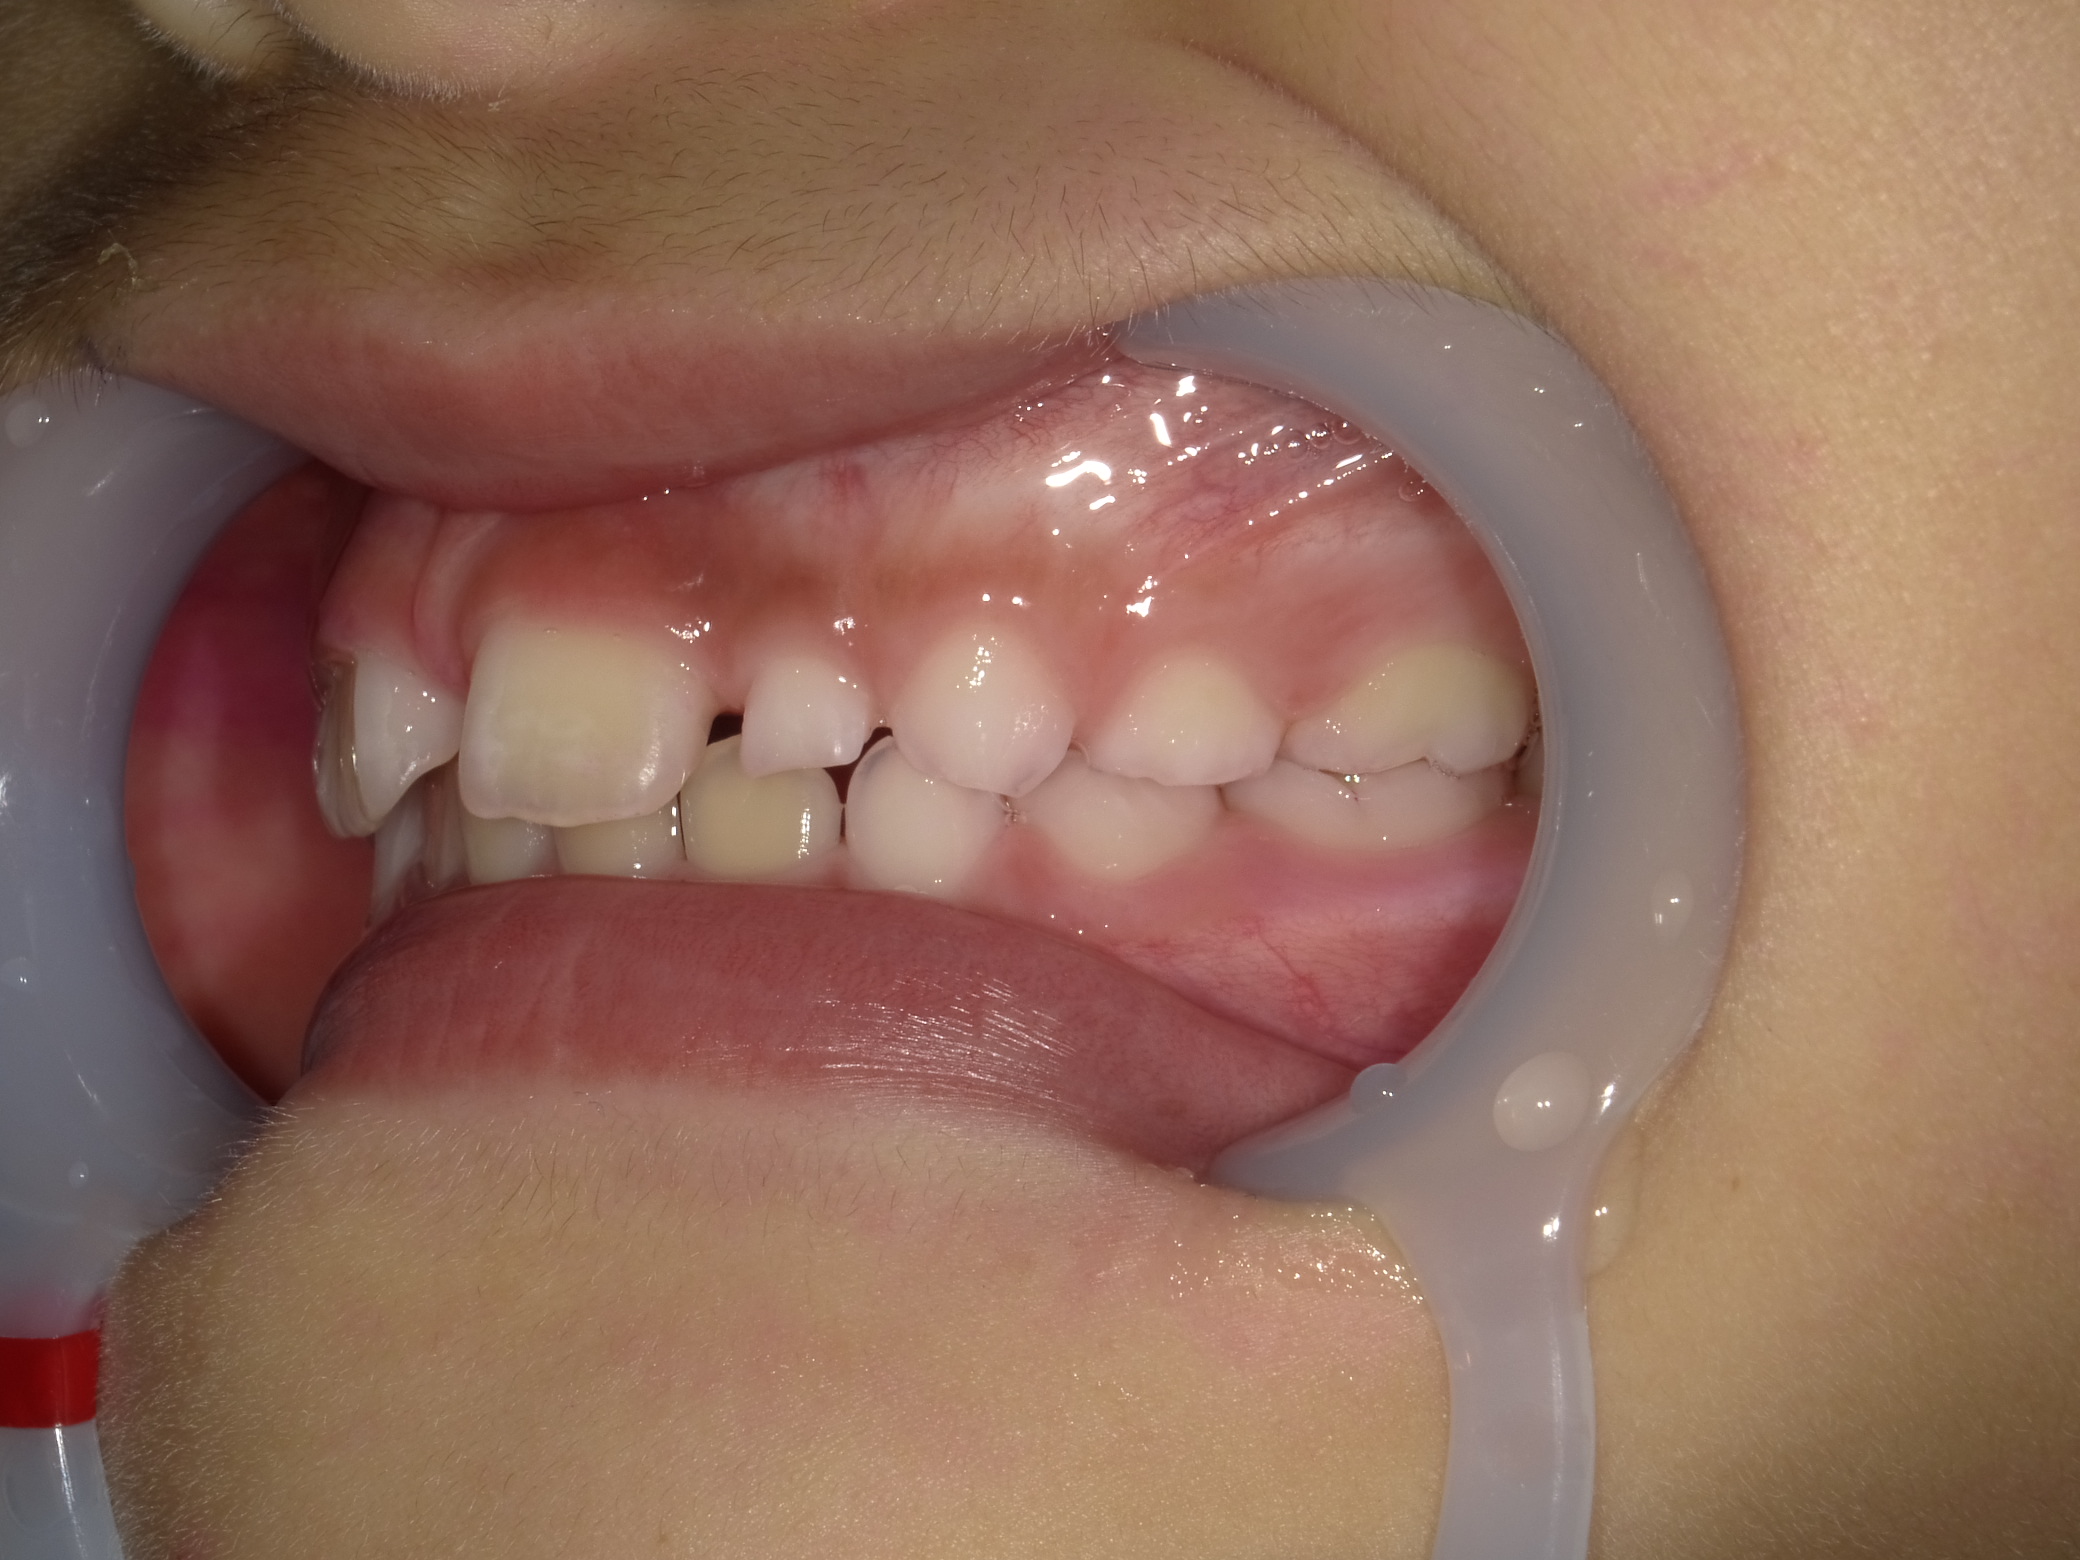

左横